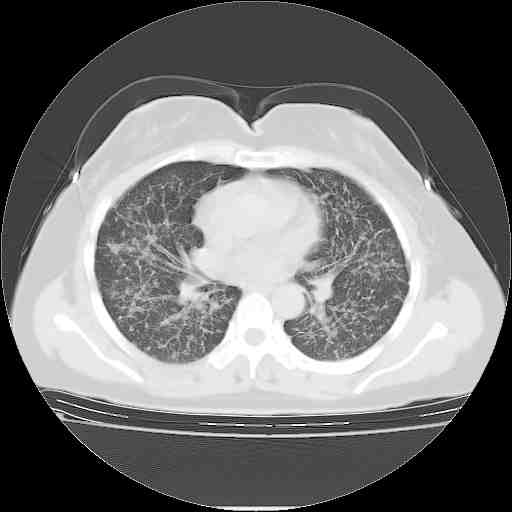

f50,肺ca治疗后,做过穿刺,确诊是肺ca,大家看看这是去年12月做的

考虑  腺癌肺内转移,治疗较前病灶缩小、减少

支持肺癌并肺内淋巴管转移,

肺癌并肺内转移,这种疾病治疗后在影像上看略有好转,不是很显著,但是肿瘤治疗效果影像只是一方面。

支持肺癌并肺内淋巴管炎,  原发灶小了,但转移较前片明显了.

支气管血管束粗而乱,考虑肺癌肺内淋巴管转移,右侧乳房第一二层软组织成份较左侧多,不会有问题吧?

支持右肺下叶周围型肺癌并肺内淋巴管炎,  原发灶小了,但转移较前片明显了.。

标准的细支气管肺泡癌呀!治疗后病情有所控制,也没治愈的迹象!